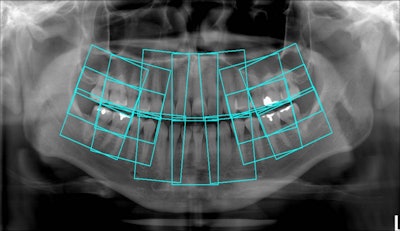

Will tomosynthesis enable panoramic bitewings?Mar 29, 2010 The software also identifies regions of interest where 18 intraoral images would normally be taken, then extracts the images from a single panoramic x-ray to create an 18-image survey. Image courtesy of Dr. Robert Langlais. close Latest in HomeNew details emerge about dentist facing suit over patient deathOctober 13, 2025Dentists aren’t feeling great about this situationOctober 13, 2025A new cavity-fighter that ditches silver in the worksOctober 13, 2025Looking back, moving forward: A reflection for National Dental Hygiene MonthOctober 13, 2025